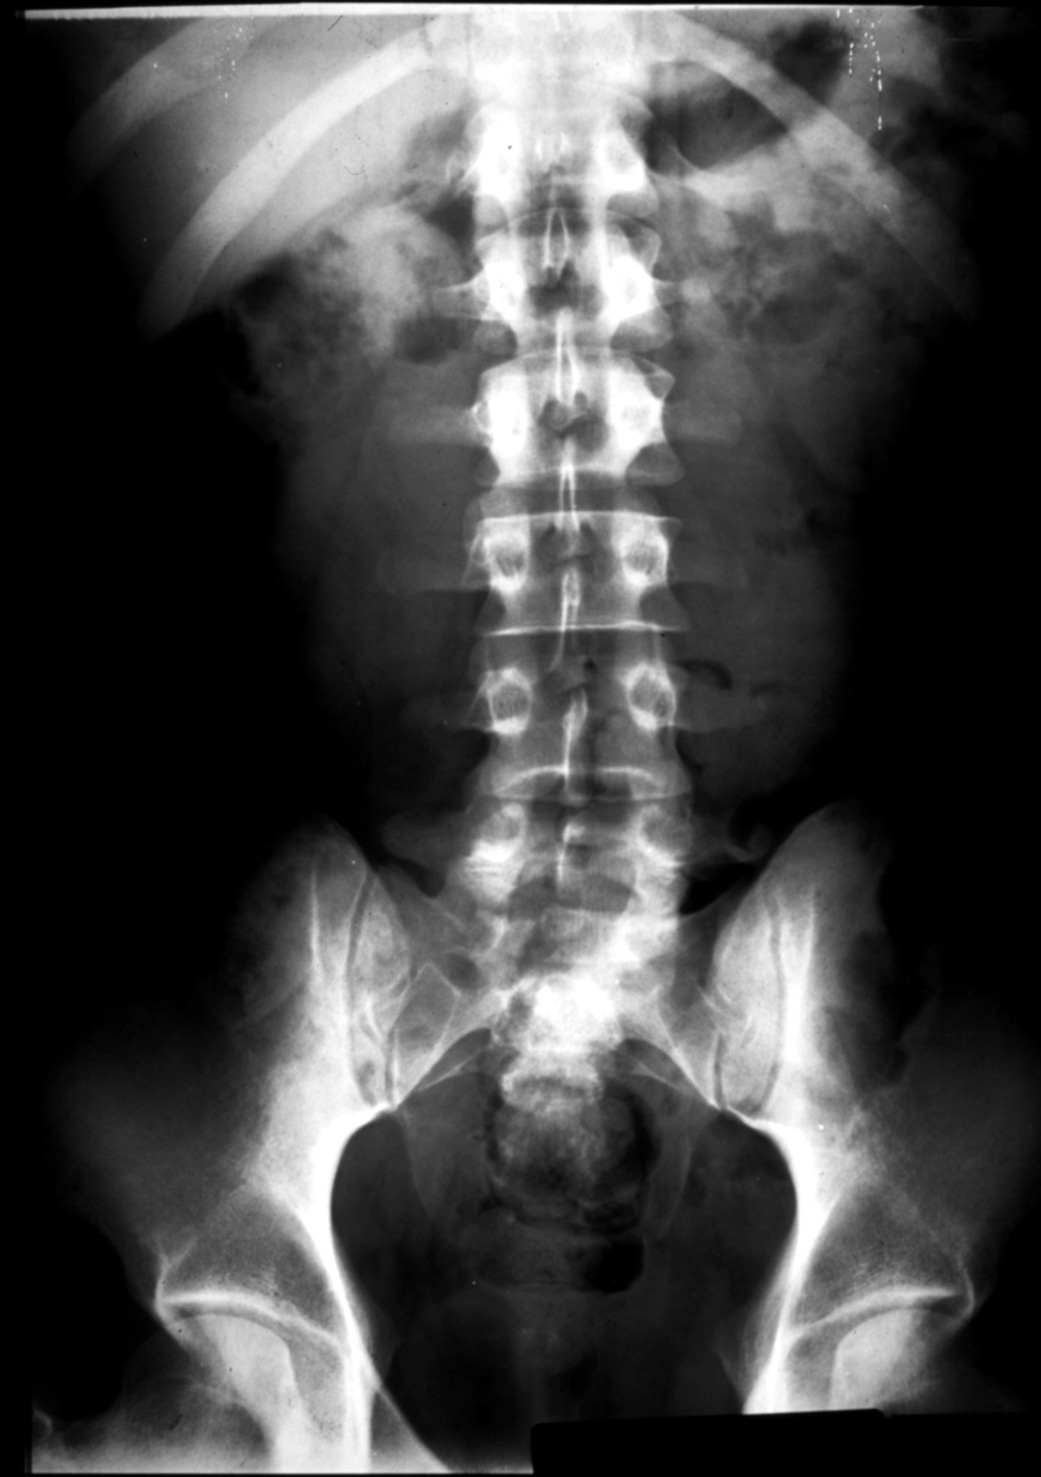

MS I 20 - Normal Abdominal Film (KUB)

Identify: antrum of the stomach, transverse colon, sigmoid colon,

psoas muscle, left kidney